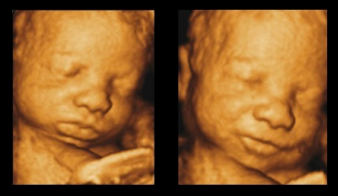

4 boyutlu ultrason, 3 boyutlu görüntülemenin zamana bağlı olarak hareketli hâle getirilmiş formudur.

Yani bebeğin yüz mimikleri, el-kol hareketleri ve vücut pozisyonu gerçek zamanlı olarak izlenebilir.

Bebeğin yüz yapıları belirginleşir

katkı sağlar. Literatürde, bebeğin yüzünü ve hareketlerini görmenin anne-bebek bağlanmasını artırdığı gösterilmiştir.